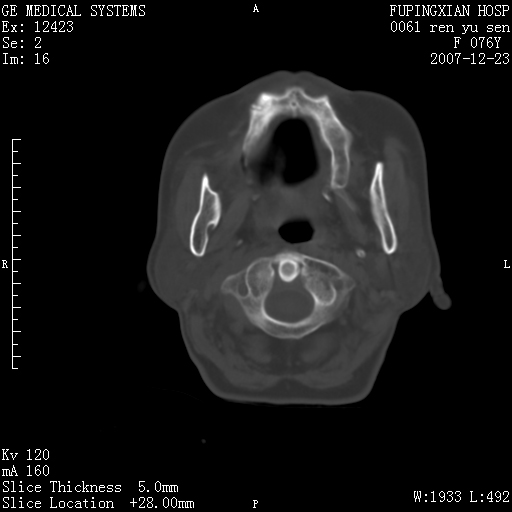

男性 76岁 下颌右侧磨牙区肿物数月, 约2.0*1.5cm大小波及颊舌侧,伴颌下淋巴结肿大。余(-)

左侧声带是否突出 请关注

喉癌?转移?是否*应考虑

右侧第四磨牙缺失,局部牙槽骨质破坏,边界欠清晰,同侧颌下及竟不见多发肿大淋巴结显示。考虑肿瘤病变可能性大,感染待排